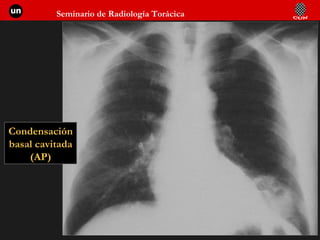

Condensación basal cavitada (AP)

Condensación basal cavitada (Lat.)

Infección pulmonar bacteriana: Evolución Inflamación de la pared bronquiolo-alveolar Extensión por poros y canales Ocupación alveolar Distribución parcheada confluente a. Resolución b. Necrosis Cavitación c. Derrame pleural Empiema Según tratamiento 1.  2.  3.

Infección pulmonar bacteriana:Evolución Inflamación de la pared bronquiolo-alveolar Extensión por poros y canales Ocupación alveolar Distribución parcheada confluente a. Resolución b. Necrosis Cavitación c. Derrame pleural Empiema Según tratamiento 1. 2. 3.